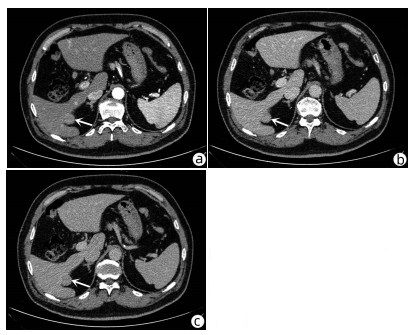

Risk factors for bile leakage after hepatectomy without biliary reconstruction: A Meta - analysis

Fei LIU, Hai LI, Qiang WU

2022, 38(3): 594-600. DOI: 10.3969/j.issn.1001-5256.2022.03.019

Abstract(1380) HTML (308) PDF (3488KB)(59)

Abstract:

Objective  To investigate the risk factors for bile leakage after hepatectomy without biliary reconstruction.  Methods  CNKI, Wanfang Data, VIP, PubMed, Embase, Web of Science, and The Cochrane Library were searched for English and Chinese study reports on the risk factors for bile leakage after hepatectomy without biliary reconstruction published up to April 2021. The method of Cochrane systematic review was used for literature screening and data extraction, and Newcastle-Ottawa Scale was used for quality assessment. RevMan 5.4 software was used to perform a meta-analysis of the extracted data.  Results  A total of 16 articles (13 in English and 3 in Chinese) were included in this study, with a total of 16036 cases. The meta-analysis showed that sex (odds ratio [OR]=1.27, 95%CI: 1.09-1.48, P=0.003), diabetes (OR=1.23, 95%CI: 1.07-1.41, P=0.003), past history of liver surgery (OR=2.50, 95%CI: 1.74-3.59, P < 0.001), anatomic hepatectomy (OR=1.58, 95%CI: 1.09-2.30, P=0.02), segment I hepatectomy (OR=2.56, 95%CI: 1.50-4.40, P < 0.001), central hepatectomy (S4, S5, S8) (OR=3.51, 95%CI: 2.80-4.40, P < 0.001), left third hepatectomy (OR=3.53, 95%CI: 2.32-5.36, P < 0.001), and intraoperative blood transfusion (OR=2.64, 95%CI: 1.93-3.60, P < 0.001) were the risk factors for bile leakage after hepatectomy. Liver cirrhosis, preoperative liver function grade, preoperative chemotherapy, and left/right hemihepatectomy were not the risk factors for bile leakage.  Conclusion  There are complex influencing factors for bile leakage after hepatectomy, and in addition to the patient's own factors such as sex, diabetes, and past history of liver surgery, intraoperative factors, such as surgical procedures, extent of hepatectomy, and intraoperative blood transfusion, are also risk factors for bile leakage after hepatectomy. The surgeon should conduct adequate preoperative assessment and perform careful operation during surgery to reduce the incidence rate of postoperative bile leakage.